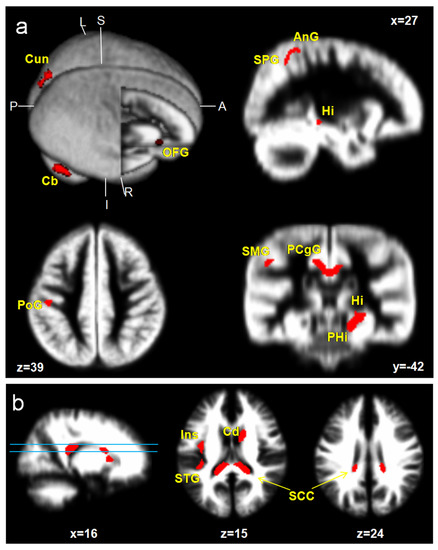

ICPP girls showed a significant increase in GM volumes; specifically, the medial prefrontal cortex (mPFC), superior parietal gyrus (SPG), supramarginal gyrus (SMG), angular gyrus (AnG), postcentral gyrus (PoG), superior occipital gyrus (SOG), cuneus (Cun), hippocampus (Hi), parahippocampal gyrus (PHG), posterior cingulate gyrus (PCgG), and cerebellar cortex (Cb) (uncorrected p < 0.001, excluded 100 voxels). However, reduced brain areas were not found in ICPP girls. Increased WM volumes are shown at the insula (Ins), caudate nucleus (Cd), and splenium of corpus callosum (SCC) (Figure 1, Table 2).

Figure 1.

Brain areas with a significant increase in GM (a) and WM (b) volumes in ICPP girls in contrast to age-matched healthy girls (uncorrected; p < 0.001, excluded 100 voxels). Hi, hippocampus; PHG, parahippocampal gyrus; PCgG, posterior cingulate gyrus; Cun, cuneus; PoG, postcentral gyrus; SCC, splenium of corpus callosum; mPFC, medial prefrontal cortex; Ang, angular gyrus; SMG, supramarginal gyrus; SPG, superior parietal gyrus; STG, superior temporal gyrus; Ins, insula; Cd, caudate nucleus; Cb, cerebellar cortex.

In this study, the brain’s developmental morphological changes and the influence of the LH on brain structure in ICPP girls were assessed by qualitative and quantitative analyses by using a VBM study based on the DARTEL algorithm and statistical approach. At first, two groups composed of ICPP girls (age 7 to 9) and the age- and sex-matched group were analyzed by a two-sample t-test (p < 0.001). The areas with increased GM in ICPP were the frontal lobe: mPFC; parietal lobe: SPG, SMG, AnG, and PoG; occipital lobe: SOG, and Cuneus; limbic system; Hi, PHG, and PCgG; cerebellum: Cb. The increased WM volumes were observed at Ins, Cd, and SCC. However, reduced WM areas were not observed. A longitudinal pediatric neuroimaging study [16] reported that the brain growth patterns across ages 4 to 22 show linear increases in WM, but in GM, they demonstrated quadratic forms in which there was increased GM in previous puberty followed by a decrease post-puberty. Specifically, the developmental curve of the frontal lobe and parietal lobe peaked at about 12 years old, while the developmental curve of the temporal lobe peaked at about 16 years old, while the GM of the occipital lobe continued to increase until the age of 20 years. Our results, specifically, the increased GM and WM volumes in ICPP girls over the age- and sex-matched group, suggest that brain development during PP showed a similar pattern to normal puberty. Thus, it is speculated that ICPP girls may be suffering an onset of synaptic proliferation and reorganization similar to puberty [16].